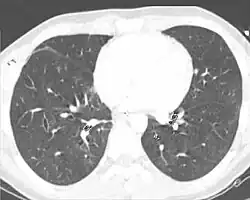

| A CT scan showing a pulmonary contusion (red arrow) accompanied by a rib fracture (purple arrow) | |

Computed tomography

Computed tomography (CT scanning) is a more sensitive test for pulmonary contusion,[8][38] and it can identify abdominal, chest, or other injuries that accompany the contusion.[43] In one study, chest X-ray detected pulmonary contusions in 16.3% of people with serious blunt trauma, while CT detected them in 31.2% of the same people.[50] Unlike X-ray, CT scanning can detect the contusion almost immediately after the injury.[48] However, in both X-ray and CT a contusion may become more visible over the first 24–48 hours after trauma as bleeding and edema into lung tissues progress.[51] CT scanning also helps determine the size of a contusion, which is useful in determining whether a patient needs mechanical ventilation; a larger volume of contused lung on CT scan is associated with an increased likelihood that ventilation will be needed.[48] CT scans also help differentiate between contusion and pulmonary hematoma, which may be difficult to tell apart otherwise.[52] However, pulmonary contusions that are visible on CT but not chest X-ray are usually not severe enough to affect outcome or treatment.[42]